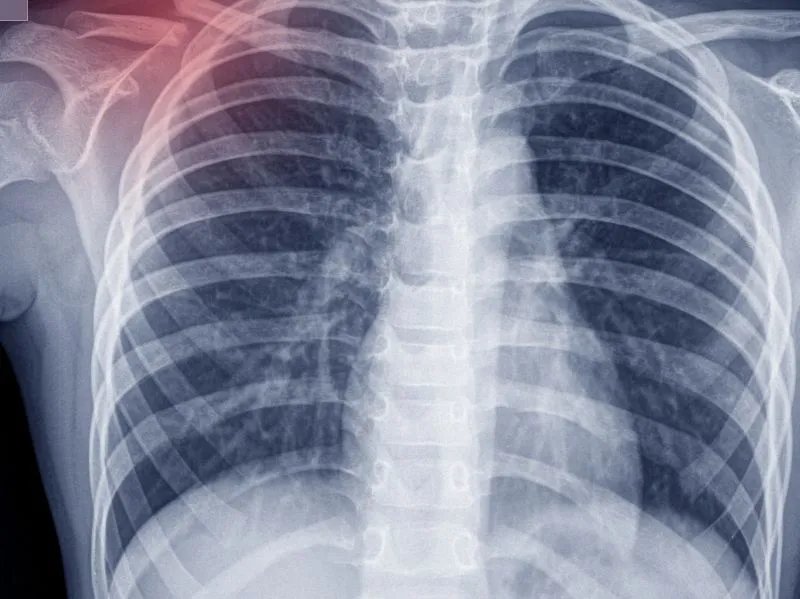

肺癌一般晚期能活多久

肺癌一般晚期可以活6~12个月,部分患者经过治疗后也可生存至5年左右。肺癌是来源于肺部组织的恶性肿瘤,晚期常通过血液,及淋巴转移到其他脏器及组织如脑,肝肾,骨胳,导致相应器官的功能障碍,以及临床症状,治疗上常采取化疗,放疗,靶向药物,免疫治疗,综合治疗可以减少复发,提高治愈率,肺癌晚期生存时间的长短,与肺癌的恶性程度,及对上述治疗效果的反应,还有就是个体差异等综合因素有关,生存时间一般不会超过5年,因此在治疗的同时,要加强营养,增强抵抗力,加强护理,以预防并发症,提高生活质量。因此肺癌晚期生存多长时间要取决于首先是病理类型,是小细胞肺癌还是非小细胞肺癌,其次的是肿瘤的分期,第3个当然是患者的体质,能不能接受规范的治疗了。肺癌做微创和做手术有什么区别吗可以选择微创手术,但是首先需要通过相关肺部ct检查以及肺组织活检,明确肺癌的严重程度以及病变的范围,在进行手术切除以后需要进行一段时间的化疗的辅助治疗。对于您所咨询的问题来看,当确诊为肺癌之后,为了控制病情的发展和恶化,目前临床上通过多年的研究发现出微创的方法来有效的控制病情的恶化和发展,也可以通过手术的方法加术后放化疗了,有效控制。无论使用哪种方法都能够治疗您的病的。肺癌晚期到最后很痛苦吗因为肺癌的晚期肿瘤增长的比较大,这个时候患者的症状会比较严重,患者还有可能会出现咯血以及吐血这样的症状,并且到了晚期癌细胞出现了大面积转移扩散的时候,这个时候患者会更加的痛苦,症状会比较多。并且因为肺部所处的胸腔中,各种组织非常复杂,当肿瘤侵入胸壁的任何一个地方,都会引发剧烈的疼痛,同时来自颈部和控制上肢的神经也要从胸壁经过,一旦受到肿瘤的压迫,也会出现疼痛。肺癌的晚期病人他到最后是比较痛苦的。